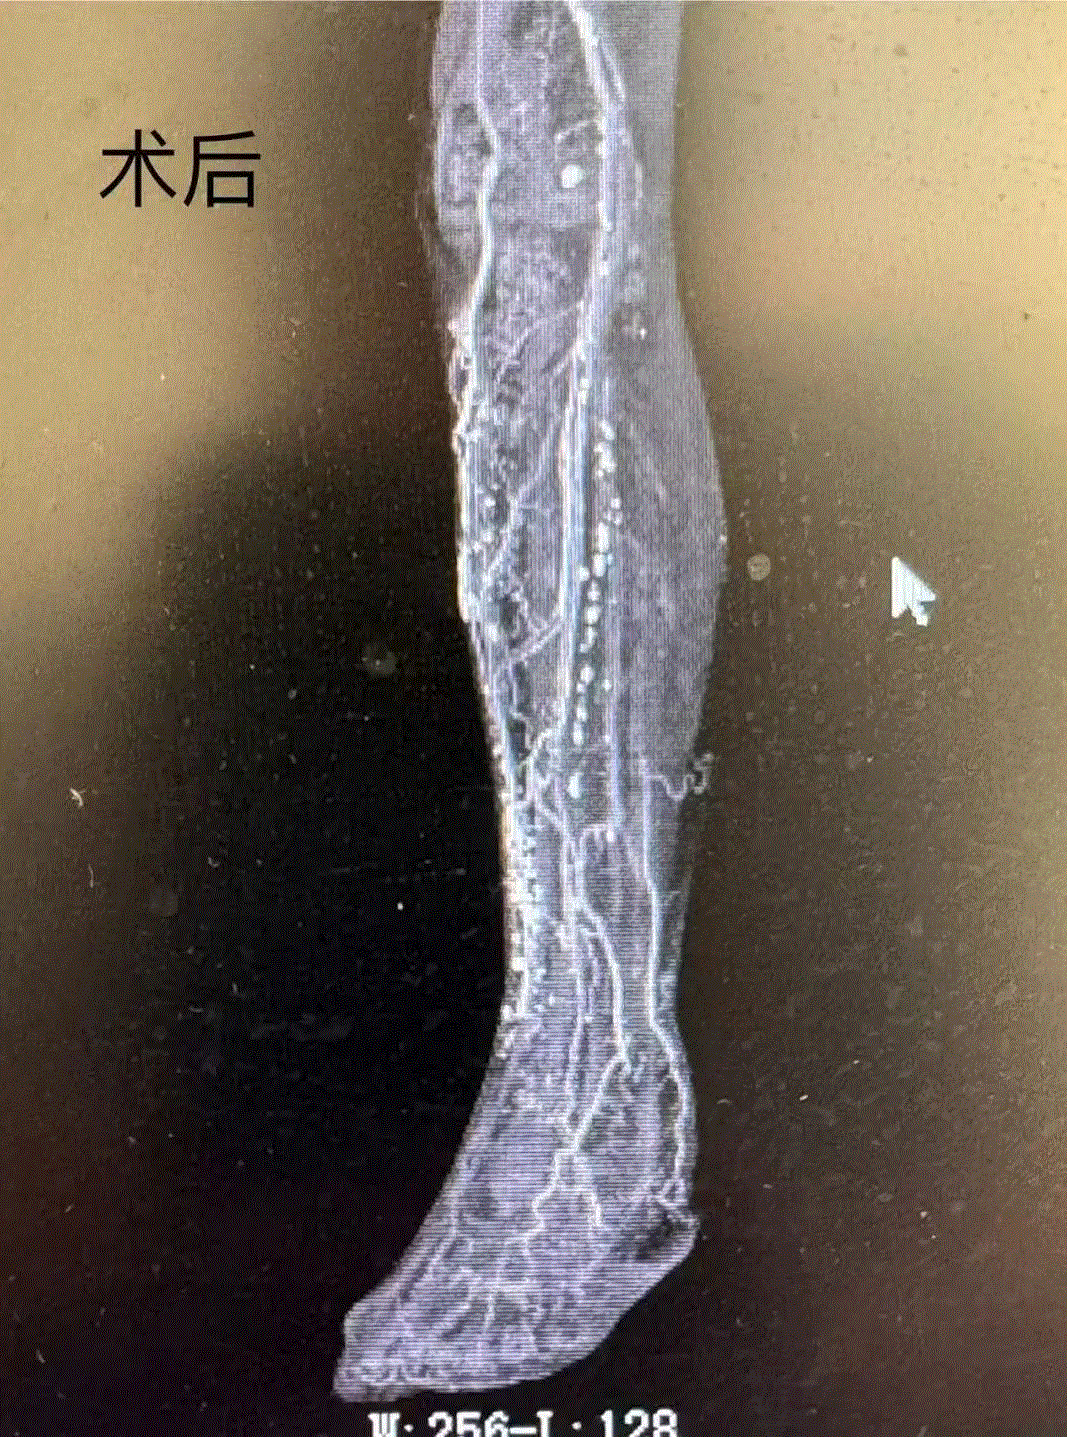

梁主任带领医疗团队反复研讨,综合考虑李大爷的身体状况和病情特点,最终决定采用 “胫骨横向搬运技术”及“足背坏死组织清创术”。术后,李大爷右脚疼痛明显减轻,心中的焦虑明显缓解,终于睡上安稳觉了。

术后两周,李大爷右脚疼痛消失,脚部肤色明显改观,皮肤温度增加约两度;术后三周脚背溃疡处完全愈合,顺利出院。